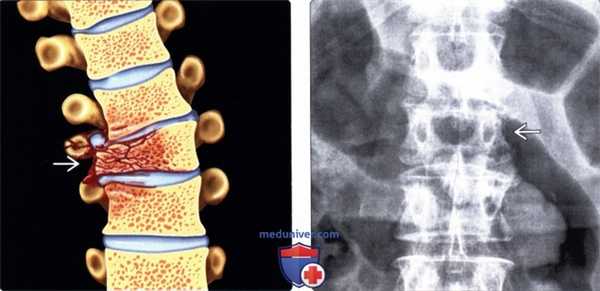

(Слева) На сагиттальной схеме показаны два типа компрессионных переломов. Наиболее распространенный тип - компрессия верхней замыкательной пластинки. Изолированная компрессия нижней замыкательной пластинки встречается редко. Обратите внимание, что на представленной схеме отражена угловая деформация передних покровных пластинок без фокальной деформации замыкательных пластинок.

(Справа) На следующей схеме представлены два других типа компрессионных переломов. Переломы, характеризующиеся вовлечением обеих замыкательных пластинок, также встречаются относительно часто, тогда как фронтально ориентированные переломы, линия которы проходит через все тело позвонка с его клиновидной деформацией, относительно редки. (Слева) КТ, сагиттальный срез: компрессионный перелом, характеризующийся угловой деформацией замыкательной пластинки и формированием «ступеньки» в области передней покровной пластинки позвонка. Не следует путать с переломом нормальную сосудистую бороздку на задней покровной пластинке тела позвонка.